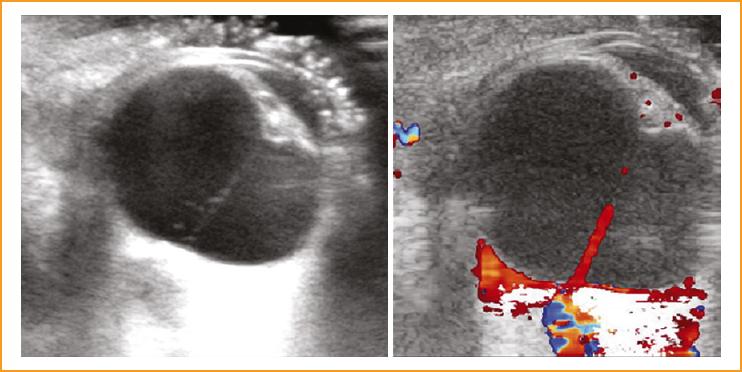

La ecografía ocular demostró una banda vítrea gruesa que se extendía desde el cristalino cataratoso hasta el disco óptico, y una retina adherida. Se observó flujo sanguíneo en la vasculatura hialoidea embrionaria (Fig. 2). La longitud axial del ojo derecho fue de 17,70 mm. La longitud axial del ojo izquierdo fue de 19,45 mm, y los detalles estructurales fueron normales en la ecografía en modo B.

Figura 2 Ecografía en modo B que muestra la lesión típica ocupando el canal de Cloquet entre la cápsula posterior y el disco óptico (forma de “I”); se detecta flujo sanguíneo en la banda retrolental y en la papila óptica.